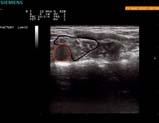

Rycina 6.16 A i B.

A. Identyfikacja splotu ramiennego z dostępu nadobojczykowego przy użyciu USG. B. Obraz splotu ramiennego z dostępu nadobojczykowego (plaster miodu); widoczna igła, przez którą podawany jest LZP (obraz USG opracował dr T. Wiśniewski).